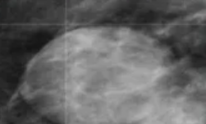

La imagen muestra un carcinoma medular, que marcadores esperarías encontrar:

A

Triple Negativo

* RE, RP, HER2 (-)

* BCRA1+

* mas mucho infiltrado linf.